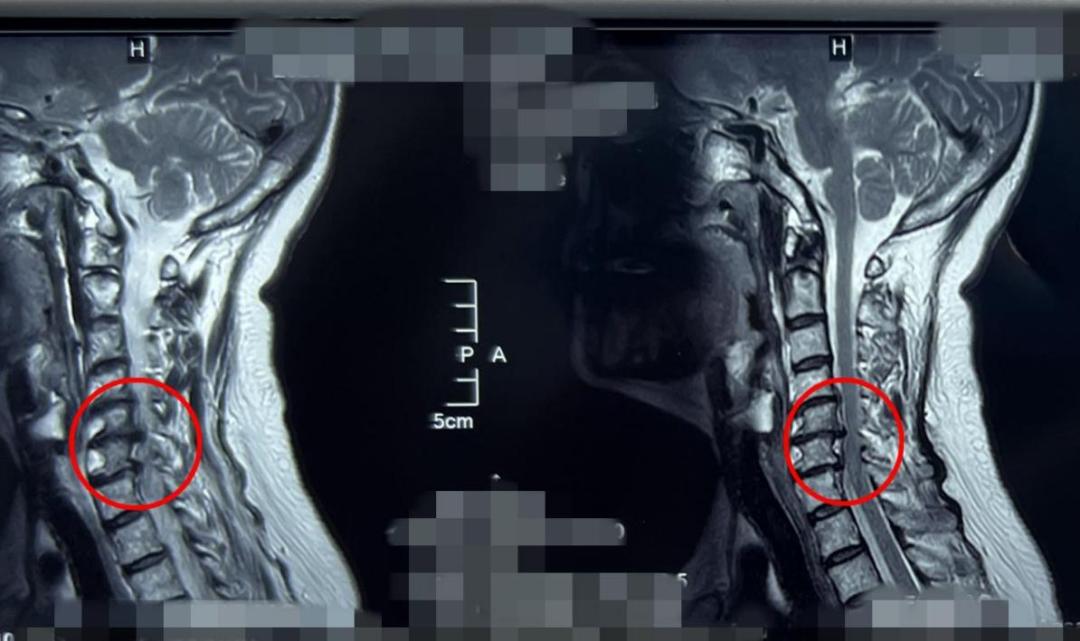

杨俊松副主任医师接诊后结合患者病史、体征和影像学资料指出,患者椎间盘突出钙化形成骨赘+神经根明显受压+椎间孔高度塌陷,建议手术干预。

脊柱病医院院长郝定均及脊柱病医院腰椎病区主任刘团江查房后指出:患者骨赘生长及神经根受压明显,且曾有过两次甲状腺手术经历,建议采用内镜下的颈椎后路keyhole手术。